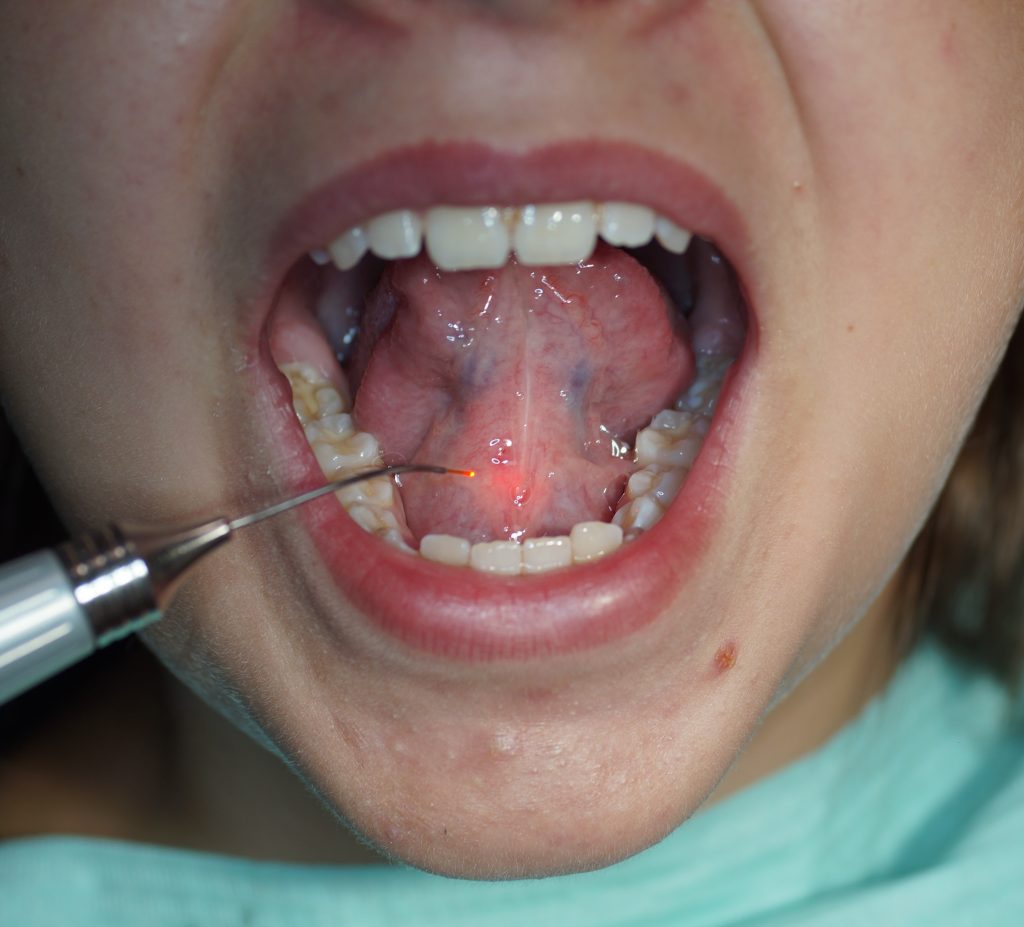

Korekta wędzidła języka przy użyciu lasera diodowego – opis trzech przypadków

Title: Correction of the lingual frenulum using a diode laser – a description of three cases

Streszczenie: Ankyloglosja jest wrodzoną anomalią charakteryzującą się skróceniem wędzidła języka, co ogranicza jego ruchomość. Ankyloglosja może prowadzić do problemów obejmujących trudności w karmieniu niemowląt czy też zaburzeń mowy. Opcje leczenia ankyloglosji obejmują tradycyjne techniki chirurgiczne: skalpel (frenotomia, frenektomia, frenuloplastyka) oraz zastosowanie laserów. Wykorzystanie lasera zarówno nisko-, jak i wysokoenergetycznego w chirurgii tkanek miękkich powoduje większy komfort zabiegu z powodu zmniejszonego krwawienia, mniejszego obrzęku i bólu pozabiegowego odczuwanego przez pacjenta.

Summary: Ankyloglossia is a congenital anomaly characterized by a short frenulum of tongue, which limits its mobility. Ankyloglossia can lead to problems including difficulties in feeding babies or speech disorders. Ankyloglossia treatment options include traditional surgical techniques: scalpel (frenotomy, frenectomy, frenuloplasty) and the use of lasers. The use of both low- and high-energy lasers in soft tissue surgery results in greater surgical comfort due to reduced bleeding, as well as lesser oedema and postoperative pain experienced by a patient.